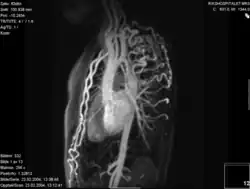

Koarktacja aorty przy użyciu różnych technik obrazowania. A. Zwężenie aorty w okolicy cieśni (strzałka). B. Obraz 3D z tomografii komputerowej z kontrastem ukazujący niewielkie zwężenie w okolicy metalowego stentu (strzałka), po poszerzeniu koarktacji – angioplastyka balonowa. C. Obraz w 3D z MRT z kontrastem ukazujący koarktację z bypassem (strzałka) omijającym koarktację. D. Obraz ukazujący duży tętniak rzekomy (grot strzałki) po uprzedniej plastyce z wszyciem łaty[13]

- ↑ Hopewell N, Hughes Marina L, Taylor Andrew M. The Role of Cardiovascular Magnetic Resonance in Pediatric Congenital Heart Disease, Journal of Cardiovascular Magnetic Resonance, 2011, 13, 51.(Koarktacja aorty. A. Ukośny rzut strzałkowy przedstawiający dyskretną, ciasną koarktację w miejscu cieśni aorty (strzałka). B. Angiogram TK 3D ze wzmocnieniem kontrastowym, pokazujący lekko zwężony stent z gołego metalu (strzałka), który częściowo pokrywa początek lewej tętnicy podobojczykowej. Grot strzałki przedstawia subtelny pseudo-tętniak na dystalnym końcu stentu. C. Angiogram 3D ze wzmocnieniem kontrastowym, obrazujący hipoplazję łuku aorty i koarktację z przeszczepem by-passu „omijającego” z tyłu (strzałka). D. angiogram MR 3D ze wzmocnieniem kontrastowym, pokazujący duży pseudo-tętniak (grot strzałki) po wcześniejszej operacji plastycznej angioplastyki. Prawdziwe światło jest pokazane z tyłu (strzałka)